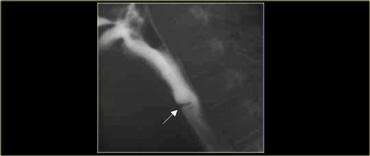

TRÁI: CT cho thấy thực quản giãn (mũi tên) dẫn đến chỉ định chụp thực quản. PHẢI: Chụp thực quản cho thấy hẹp (mũi tên) tại mức khe hoành.

Bên trái là một bệnh nhân khác bị achalasia.

TRÁI: Thực quản giãn (mũi tên) được chiếu phía sau nhĩ phải. GIỮA và PHẢI: Hẹp thuôn nhẵn ngay trên cơ hoành (mũi tên).

Trong quá trình soi huỳnh quang, quan sát thấy một số nhu động với hình ảnh hẹp thuôn nhẵn điển hình ngay trên cơ hoành (mũi tên).